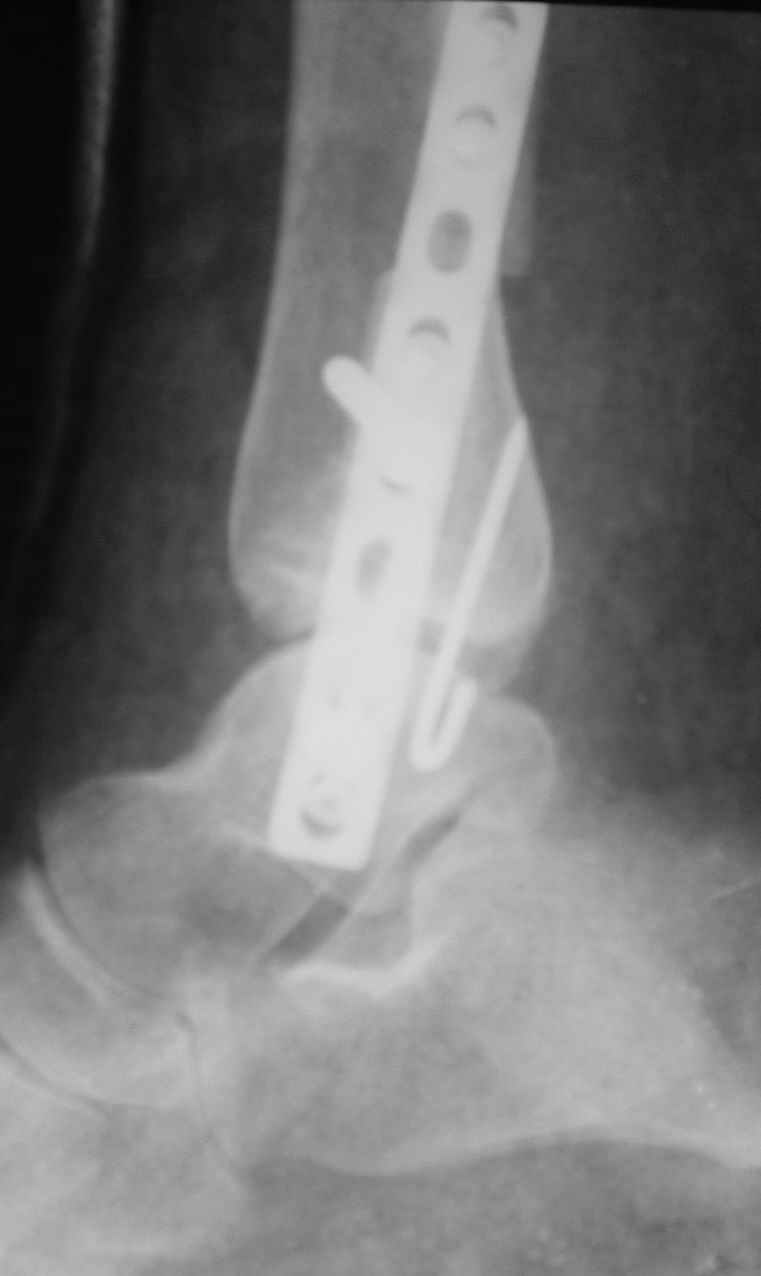

Уважаемые коллеги! Персонально, дорогой доктор Джолдас. Не знаю, почему почта к тебе не проходит - у меня почтовая программа "Bat", снимки в JPG. Выставляю через форум. 10 апреля я показывал снимки больной с застарелым переломо-вывихом голеностопного сустава. 9 июня прооперировал, снимки прилагаю. R-контроль через месяц ходьбы на костылях, все стоит также. Разрешил частичную (20кг) нагрузку на ногу, пока жалоб нет. Ход операции - сагиттальная остеотомия по линии неправильно сросшегося перелома малоберцовой кости, остеотомия с формированием внутренней лодыжки, попытка вправления подвывиха неудачна из-за того, что "не хватало" длины малоберцовой. Остеотомия малоберцовой кости выше синдесмоза. Остеосинтез.

На снимках хорошо сохранный голеностопный сустав, подвывих устранен, суставная щель одинаково прослеживается со всех сторон, небольшая нехватка длины малоберцовой и немного выступает пластина, а так в целом репозиция и фиксация удалось. Иногда, синдесмотический шуруп мы вводим немного длиннее, примерно на 3мм за медиальный кортекс, при переломе шурупа после нагрузки, шуруп легко удаляется с медиальной стороны. После 6 недель в гипсе можно разрешить нагрузку.